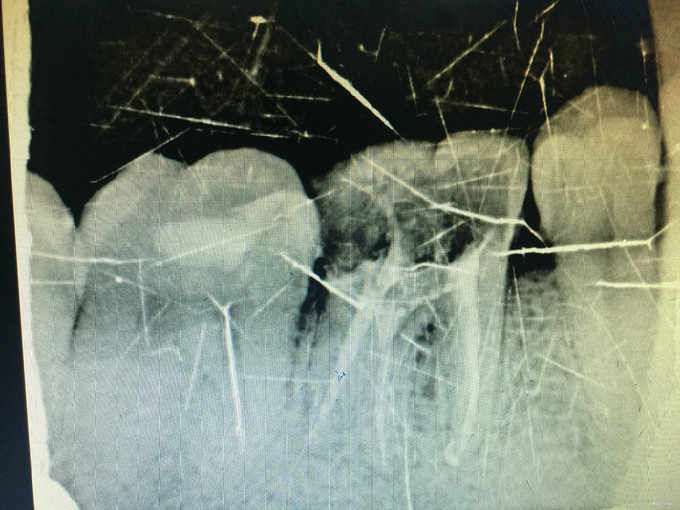

临床检查:46充填物未脱落,探疼(+—),冷(—),叩(+),松动度(-),牙周正常. 辅助检查:X线示46充填物累积髓腔,根尖周牙周膜略增宽。

诊断:46慢性牙髓炎 治疗:经患者知情同意后,46局麻去除原有充填物降牙合,开髓寻找根管口,建立直线通路,扩通根管,确定工作长度。S3/EDTA凝胶镍钛器械,低浓度次氯酸钠冲洗根管,预备至35/04,氢氧化钙诊间封药,一周后复诊,试主尖X线示恰充,试干根管,导AH-PLUS糊剂,VDW热压胶垂直加压根充,术后见根管恰充,暂封调合抛光。